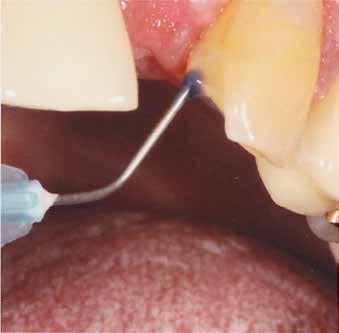

Massimiliano Trombin, dr. Roland Mantsch, Lorenzo Willsch (Németország) 1. a kép 1. kép 2. kép 3. kép

Az egyszárnyú ragasztott híd mellett döntöttünk (1. a kép)

Mivel a szemfogak általában nagyon közel vannak az antagonistához, kettes pótlására a szárnyat inkább a nagymetszőre szoktuk tervezni. Ehhez persze invazív preparációra van szükség – érintetlen fogak esetén ez lehetőleg kerülendő.

A bemutatott esetben azonban könnyen döntöttünk, mivel a szemfog disztális részén nagy tömés volt. A defektust bevontuk az eset megoldásába.

A preparálást követően Provil-lal vettünk lenyomatot.

Most következett a legfontosabb lépés: a szárny belső felületét HotBond-dal fújtuk le (14. kép). Ez üvegszerű, savazható kerámia, amely beszívódik a cirkonba, és optimális kötést eredményez a pillérfogon.